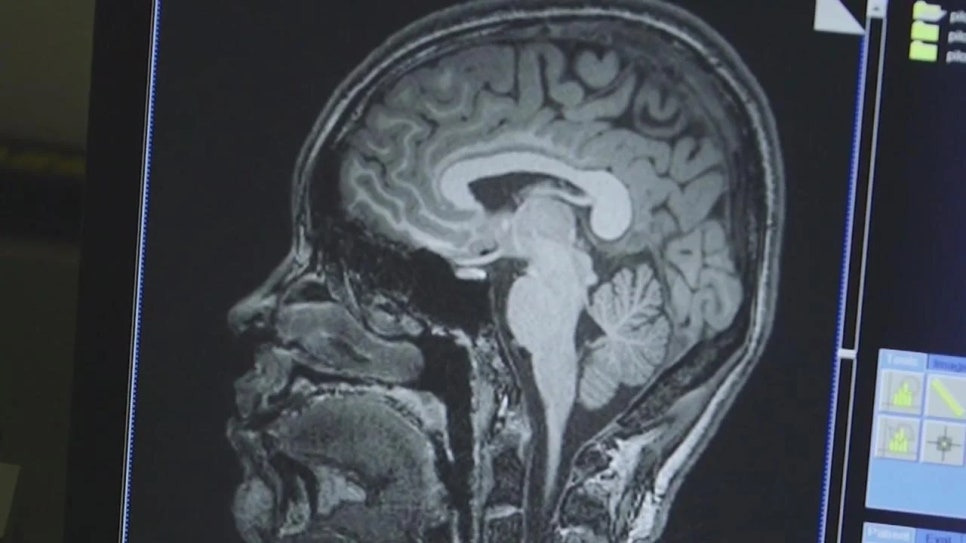

미국 피츠버그 대학교 연구진이

알츠하이머병의 증상을 발현하기 무려 10년 전부터 확인할 수 있는

바이오마커 검사를 개발했다는 소식이었어요.

뇌와 뇌척수액 속에 존재하는 극미량의 응집된 타우 단백질을 감지해

알츠하이머병을 조기에 예측할 수 있다는 이 연구는,

피츠버그 대학교 연구진이 개발한 바이오마커 검사는

뇌와 뇌척수액 속 극미량의 응집된 타우 단백질을 감지함으로써,

알츠하이머병의 증상이 나타나기 수십 년 전부터 위험 신호를 포착할 수 있게 해요.